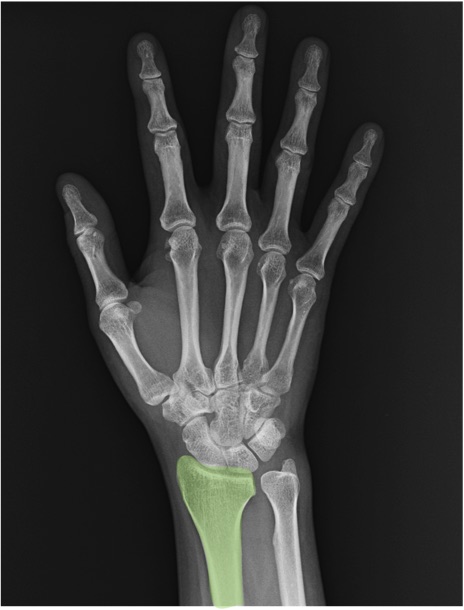

橈骨(radius)の手関節レントゲン画像における正常解剖

症例